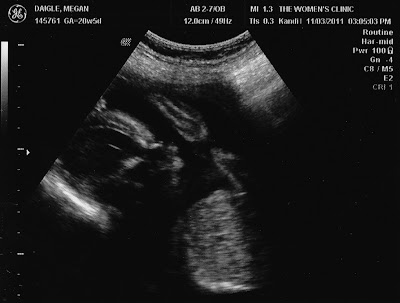

It's a GIRL!!

Yes indeed! I'm here to say motherly intuition played in and won out on this one: I would have guessed its a girl. I didn't really say such as I am not God and it was a guessing game for me until the sonogram showed. Zoë Grace is measuring perfectly for her due date of March 17, 2012!

I have a feeling my little "Bean" is going to be a cuddle bug. EVERY ultrasound we have a snapshot of her laying on her side with her hand under her head. She at least likes to get comfy for sure!

Zoë Grace with her hand (very hard to see) snugged up tight under her cheek :) So precious to me!

She also just LOVES to change position and see how flexible she can show herself off to be. There were several times we caught her with her legs pulled completely to her chest. We also caught her like this:

If you notice, that line above her head is her leg stretched completely out above her head! Silly girl!

Oh...and it was soo cute: just before the tech caught the first pic, we got to see her take a HUGE yawn. Then she snuggled up. Ben says she's going to be a little gymnast :)

• Your heart continues to beat healthy and strong at 144 bpm

• You are extremely flexible, my dear, and LOVE to show it off :)

• You have begun to practice swallowing and definitely like to yawn - we caught you take a big one just before you curled up for some sleep!

• You weigh a whole 14 oz which Doc says is just right.